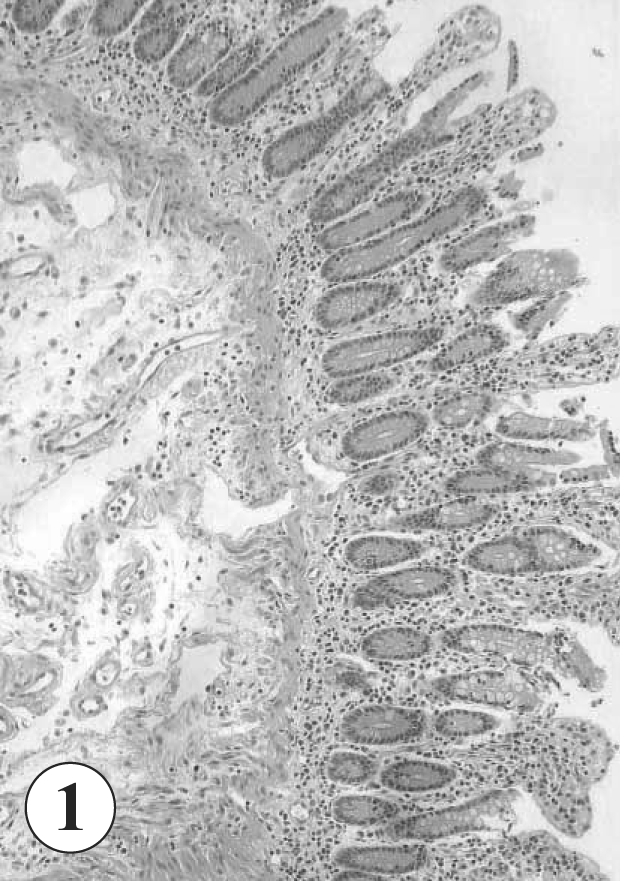

3). The worm showed a characteristic appearance of its large oral sucker, small ventral sucker, seminal vesicle, pars prostatica, vitellaria, and a ventral pit surrounded by strong muscle fibers (

Fig. 3), and was diagnosed as an adult

G. seoi. The patient was treated with 10 mg/kg praziquantel, but unfortunately died due to aspiration pneumonia 3 months after the palliative operation.

Yu et al., 1993). In the worm section, the genital pore and testes were invisible, and the number of vitellaria and the shape of the seminal vesicle were unrecognizable. However, the presence of a ventral pit was suggested, by the presence of strong muscle fibers near the ventral sucker in

Fig. 3. Moreover, the patient's residence, i.e., Mokpo-city, supports the diagnosis of

Fig. 3Magnification of the sectioned worm in

Fig. 2. Abbreviations. pp; pars prostatica, sv; seminal vesicle, vp; ventral pit, vs; ventral sucker, vt; vitellaria. H-E stain. x 200.